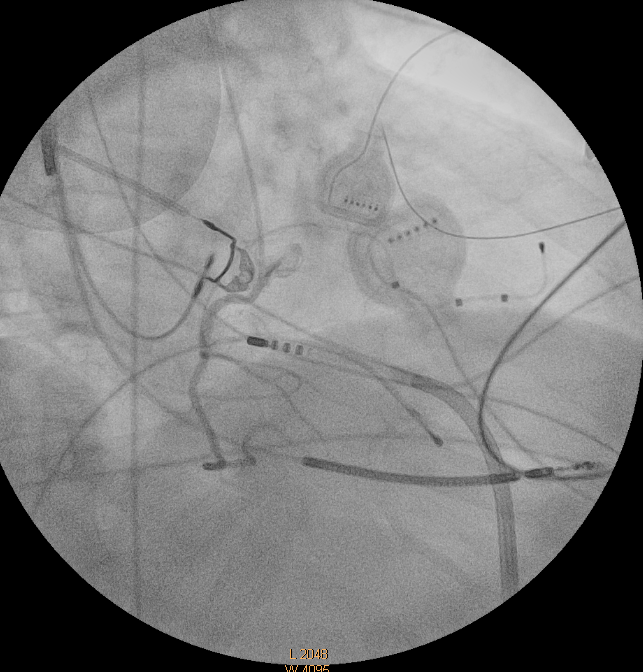

For the first time, the Electrophysiology Laboratory of the 2nd University Cardiology Department at Hippokration General Hospital of Thessaloniki has successfully performed an epicardial ablation procedure for ventricular tachycardia.

The pioneering procedure was carried out in two patients with a history of dilated cardiomyopathy who had suffered repeated discharges from their implanted biventricular defibrillators. In such cases, epicardial ablation often provides the only effective access route to treat life-threatening arrhythmias, especially in high-risk patient groups such as those with dilated cardiomyopathy or arrhythmogenic right ventricular cardiomyopathy.